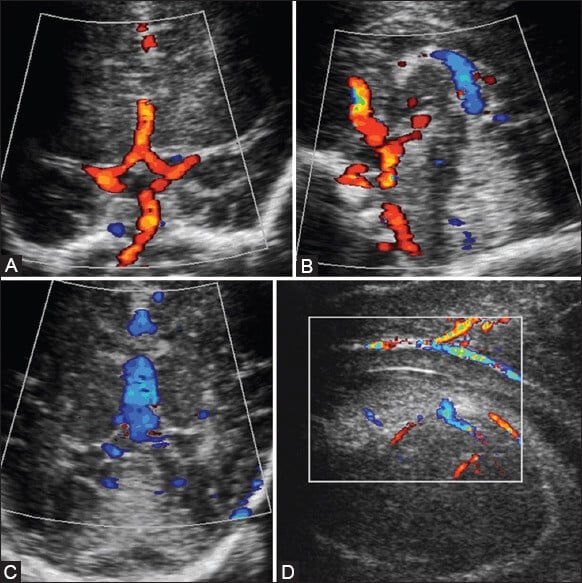

Além disso, utiliza-se imagens com Doppler colorido e espectral para avaliar estruturas vasculares, como o círculo de Willis e a veia de Galeno.

Nos casos de agenesia do corpo caloso, a artéria cerebral anterior pode apresentar um padrão característico, descrito como “sunburst”, visível com precisão nos exames em escala de cinza e Doppler.

Além disso, o ultrassom pode revelar condições associadas, como colpocefalia e outras anomalias na fossa posterior.